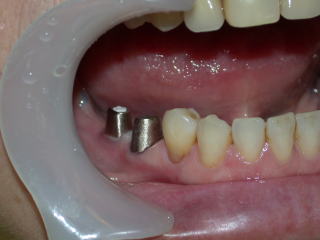

ヒーリングアバットメント装着。

外れた右下5番も一緒に治療します。

ガム模型上でカスタムアバットメント作製。